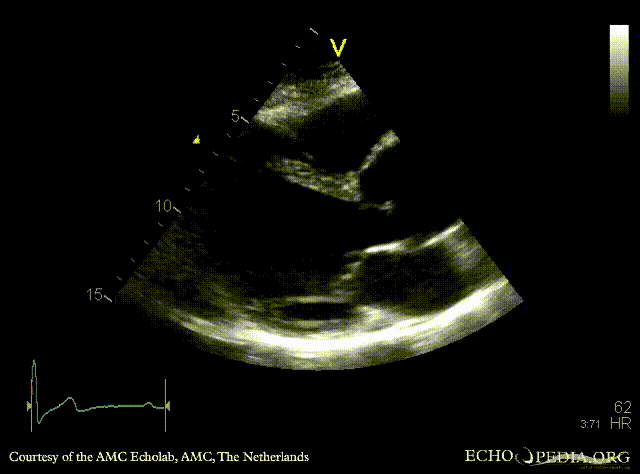

PLAX: dilated aortic root PLAX: 2-D measurement of aortic root